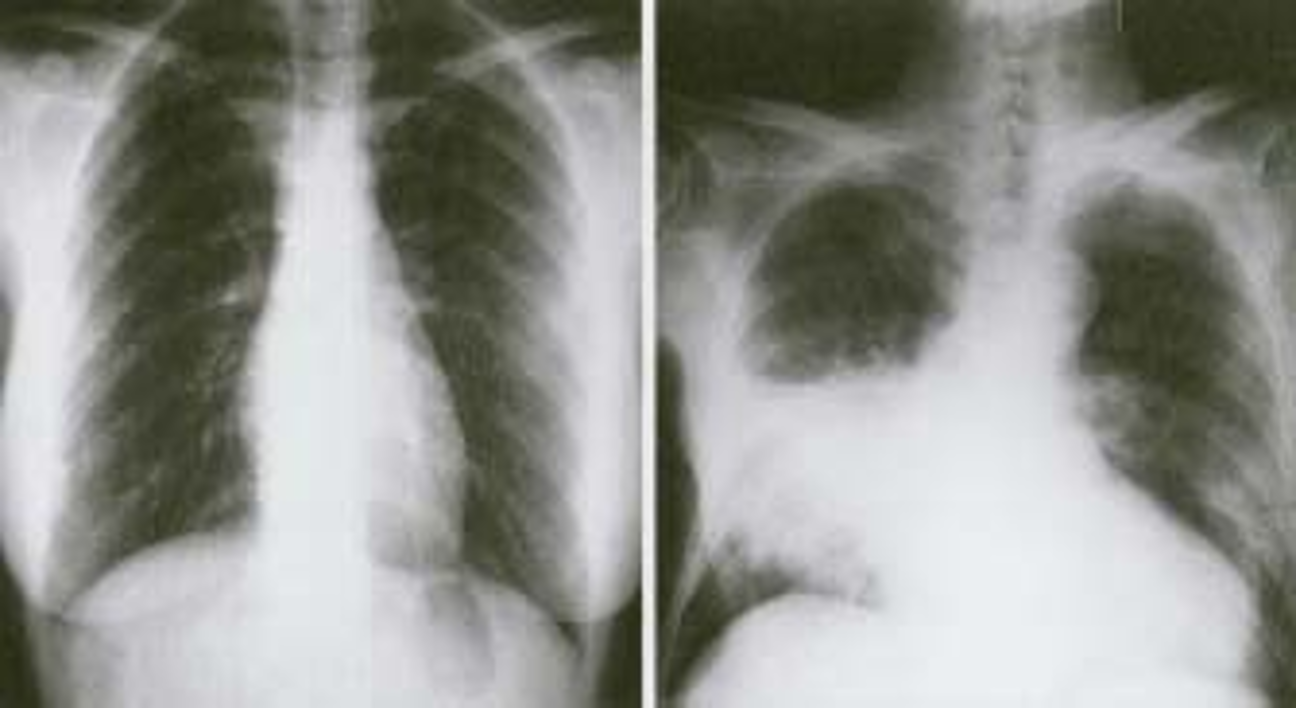

- Bacterial pneumonia:

- Lobar consolidation (air bronchogram) occasionally with parapneumonic effusion. Pneumatocoele and abscesses suggest staphylococcal pneumonia

Right lower lobe consolidation in a patient with bacterial pneumonia.

RT. lower lobe; Lobar pneumonia: Opacity of one or more pulmonary lobes & Presence of air bronchograms

- Right lower lobe is most commonly affected by pneumonia

- Spine blackness increased reversibly (Spine sign); lower part opaque